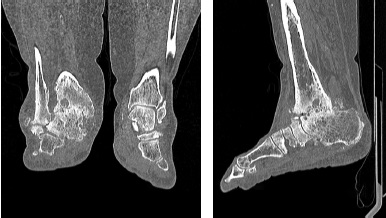

Radiological examination methods (radiography, MRI, MSCT of the ankle joint) showed undoubted signs of posttraumatic AVN of the talus and its complications in the form of collapse of the talus, multiple cysts of the tibia, talus, calcaneus, etc. (Fig. 2, 3, 4).

Fig. 2. X-rays of the ankle joints: a — AP X-ray: posttraumatic degenerative distal tibial diastasis, suspicion of gross valgus deformity of the ankle area, 3 stage of posttraumatic deforming osteoarthritis of the ankle joint; b — X-ray in lateral projection: collapse of the talus body, arch of the foot, 3 stage of deforming osteoarthritis of the ankle, talonavicular joint, ankylosis of the subtalar joint

Fig. 3. MSCT of the ankle joints. Right-sided 3 stage osteoarthritis of the ankle joint. The right ankle joint is deformed. Articular surfaces are clear, uneven, subchondral osteoarthritis of articular surfaces with cyst-like rearrangement. The articular gap is threadlike narrowed. Outcome of posttraumatic aseptic necrosis of the right talus